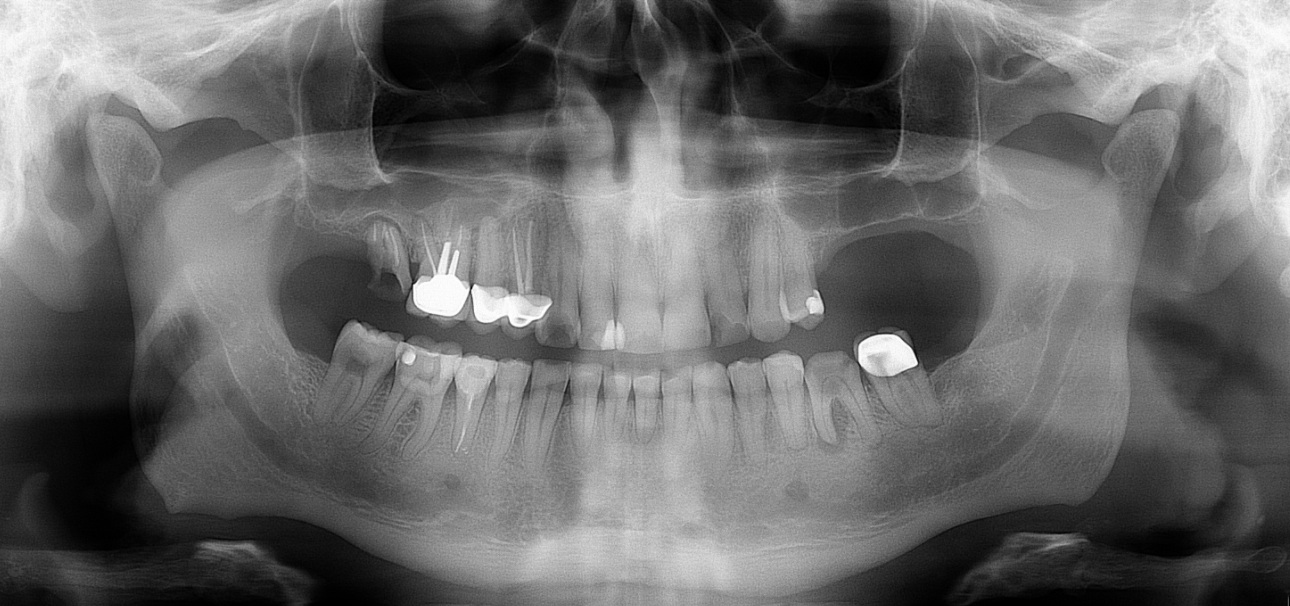

Klinikai és radiológiai vizsgálatok alapján megállapítottam, hogy a túlterhelés (parafunkciók) jelei látszódnak a fogain is: abfrakciók – nyaki kopások és attríciók –, rágófelszíni kopások is kifejezettek voltak. Harapása igen bizonytalan tartományban mozgott, nem volt egy stabil helyzet, amelybe határozottan össze tudott volna zárni (csak kereste a megfelelő pozíciót.) TMI-vizsgálat során reciprok crepitációt (kattanás nyitáskor-záráskor is), myofascialis eltéréseket (hypertrófiás musculus masseter – túlterhelt rágóizom) és beszűkült mozgáspályákat találtam. Emellett sajnos a nem megfelelő szájhigiénés szokások miatt a fognyakak „sérült” részein szuvasodások is megjelentek, illetve a bal alsó hatos és a jobb felső hetes fog már oly mértékben destruálódott, hogy el kellett távolítani őket.

A nagy kiterjedésű szuvasodások ellátására, továbbá a harapási forma és ezzel együtt az ízületi panaszok megszüntetésére full kontúr cirkón pótlást terveztem, melyet individuálisan a rendelőnk ARCUSdigma készülékének segítségével készítettem el.

Első lépésként előkészítettem a fogakat a pótláshoz (szuvas léziók eltávolítása, csonkkiegészítések kompozit tömőanyaggal, csonkpreparálás), és levettem a szükséges lenyomatokat.